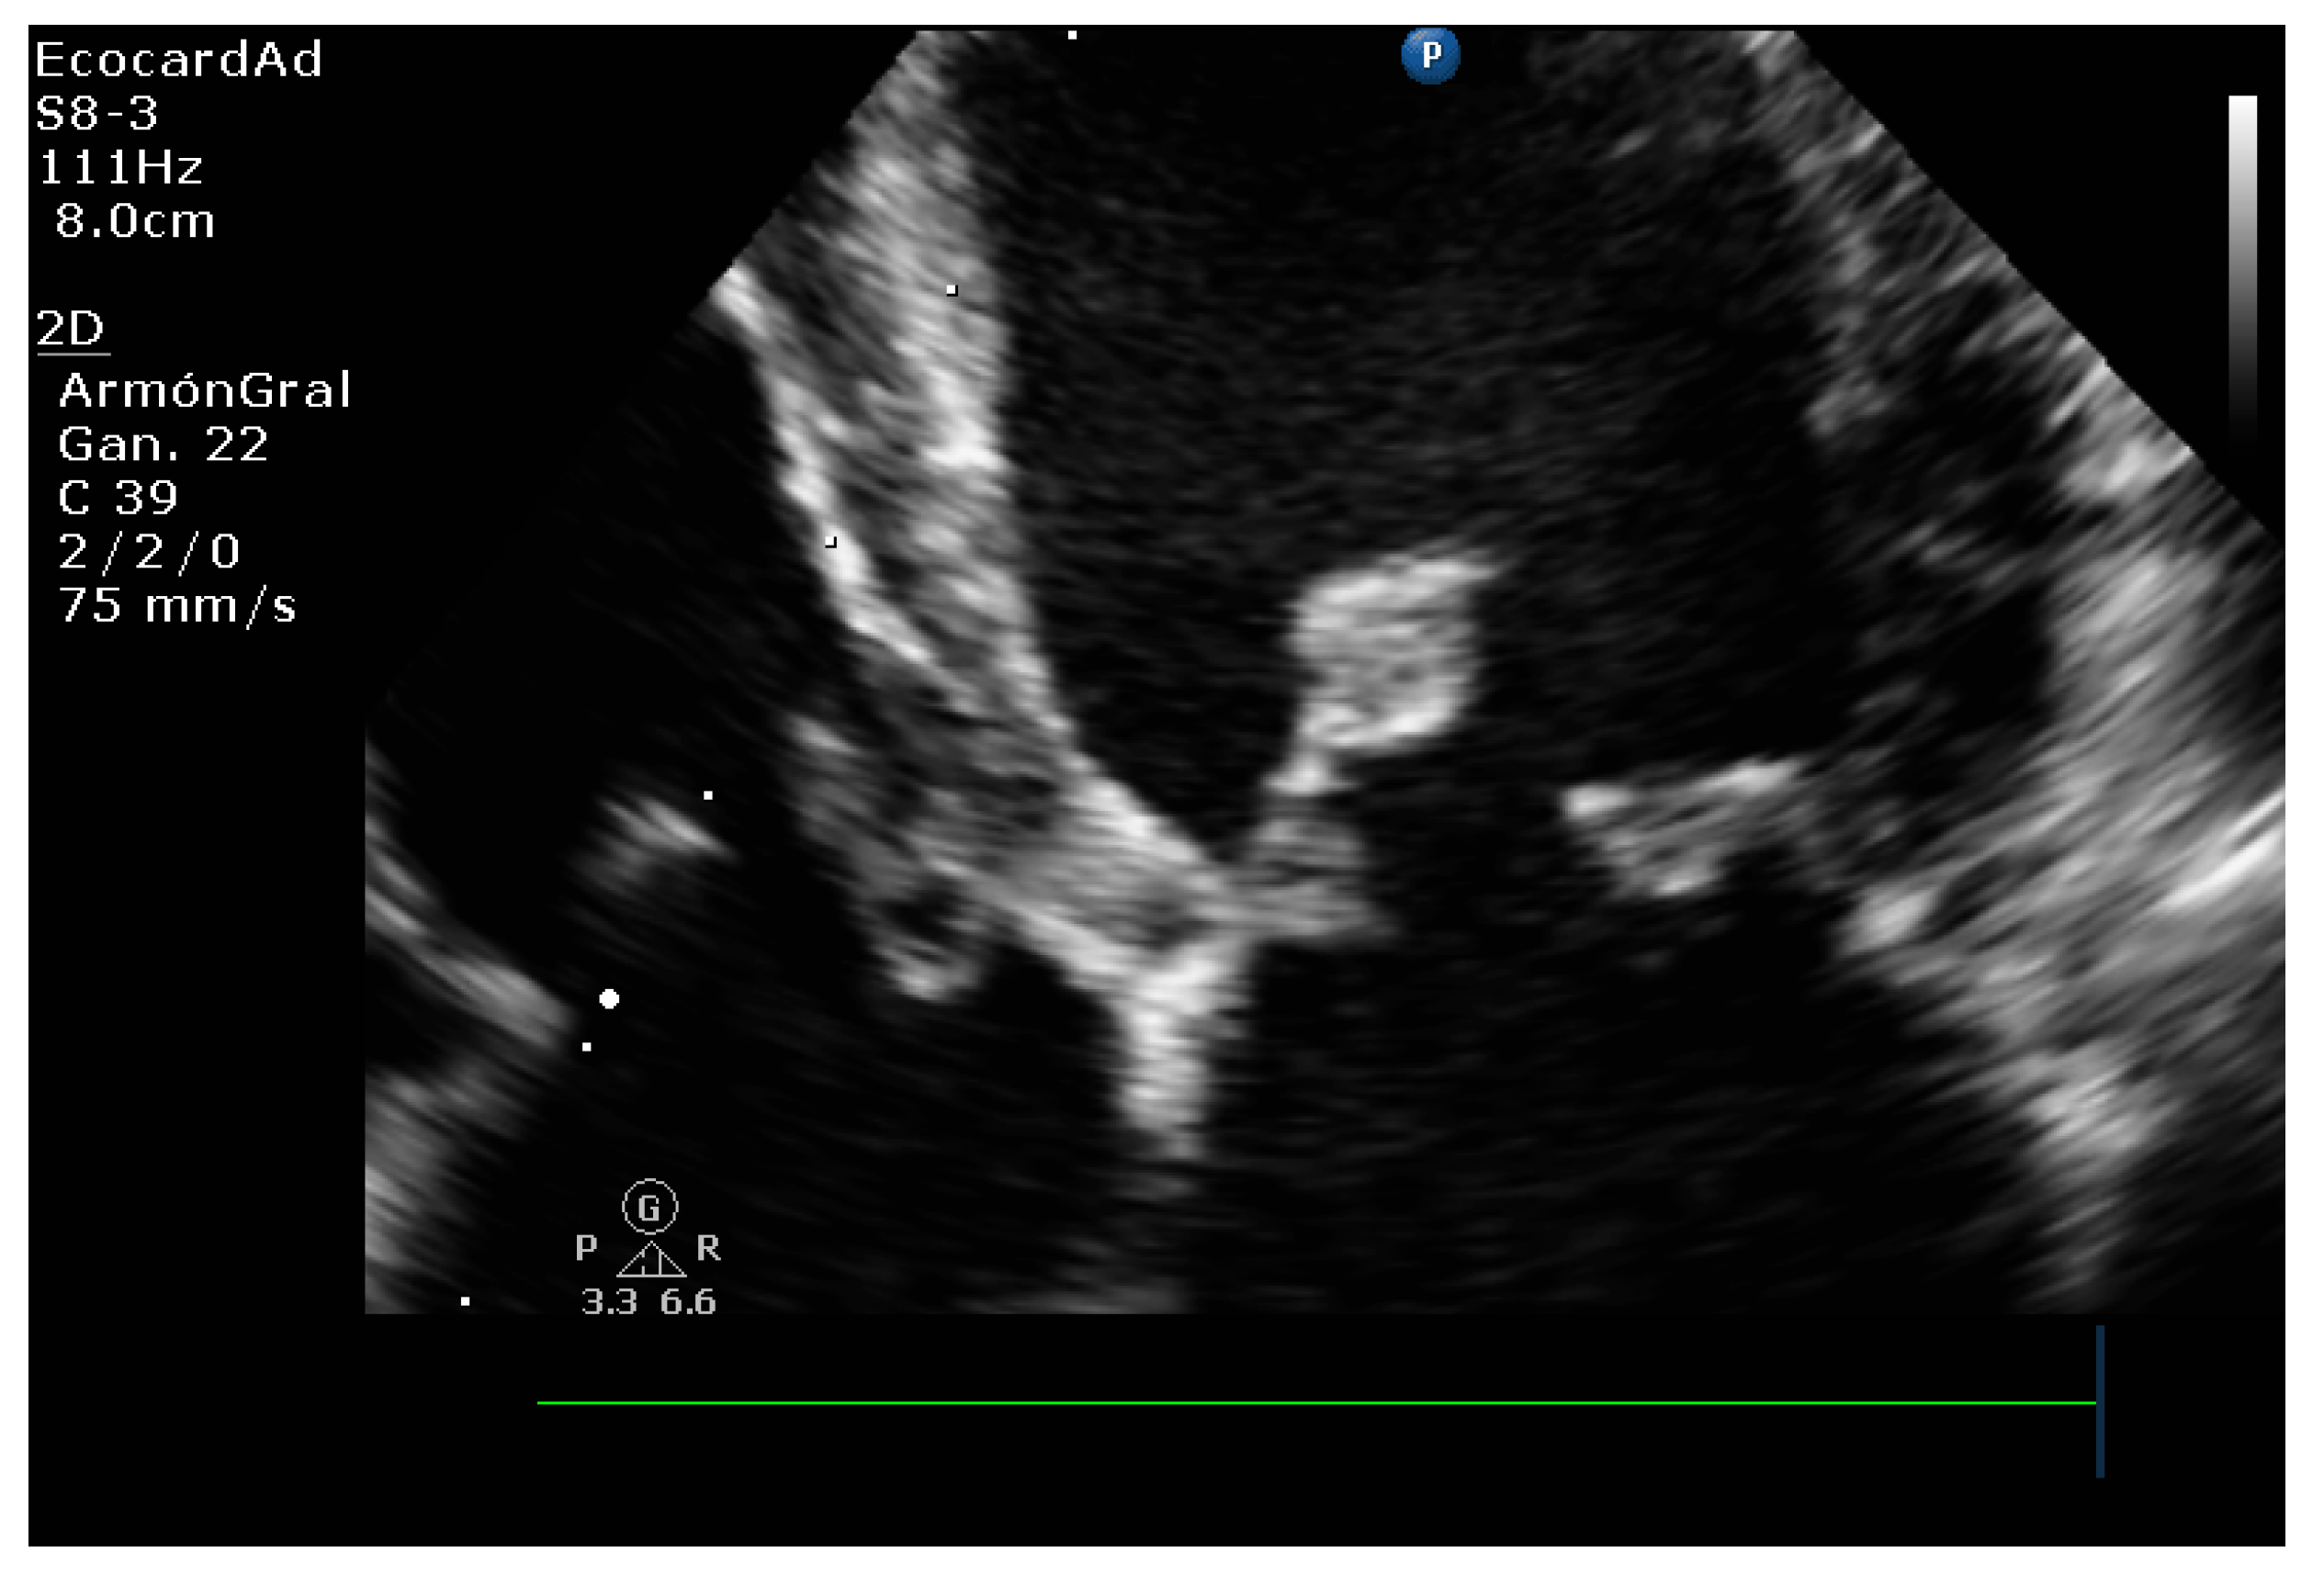

4.8.3. Degree of Myxomatous Degeneration

4.8.4. Mitral Valve Prolapse